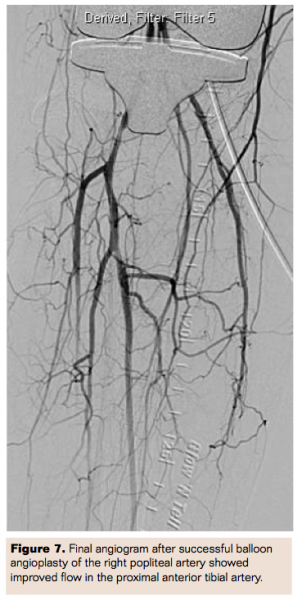

Balloon angioplasty of the right popliteal artery was performed from the groin access using a Charger 5.0 mm x 60 mm balloon followed by a Charger 6.0 mm x 60 mm balloon (Boston Scientific) with excellent results. However in the right lateral view while balloon was inflated, there was a hint of suspicion that the implant might be pushing on the popliteal artery (Figure 6). It was decided at that time not to deploy a Supera stent (Abbott Vascular), which is FDA approved for this location.

With flow restored in the popliteal artery, the proximal anterior tibial artery that was previously occluded seemed to have some flow as well, which we thought would improve with time (Figure 7). The patient was transferred to the recovery area. Because of the suspicion for knee implant compression on the popliteal artery, ultrasound of the right lower extremity performed, which showed occlusion of the popliteal artery again. At that time, the decision was made not to further pursue endovascular management.